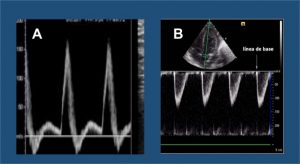

Para representar la señal Doppler, se usa una gráfica (ver figura) en la que las frecuencias Doppler o las velocidades se muestran en el eje vertical y el tiempo en el horizontal, mientras que la amplitud o potencia de cada componente del análisis se presenta en escala de grises

Si el flujo sanguíneo se acerca al transductor, se representa en la imagen por encima del eje horizontal (A); y si se aleja, por debajo del eje (B).